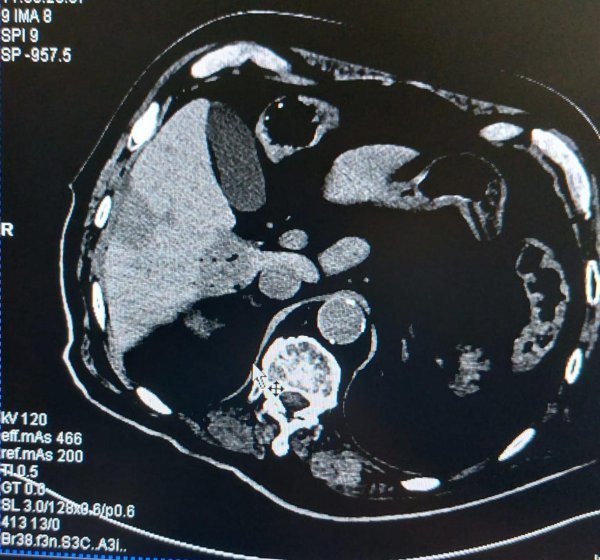

Tumor

• Luka Novosel i tim

• tumor

• operacija

KBC Sestre milosrdnice Izvor: Promo fotografije / Autor: KBC Sestre milosrdnice